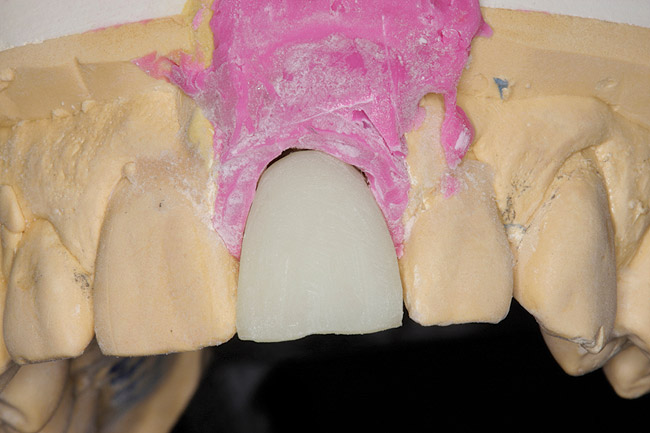

Fig 2. Cast altered so indexed transfer coping can seat with appropriate analog attached.

Figure 2

The restorative dentist can duplicate the contours of the extracted tooth for the new screw-retained provisional following these instructions: First make an index of implant position with a transfer coping. Then, either pour up a working cast or alter the cast used to fabricate the surgical guide. The cast is altered in the area of the implant fixture to allow the indexed transfer coping to seat with the appropriate analog attached (Figure 2).